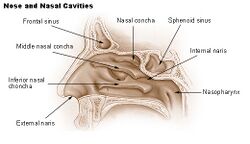

Internal anatomy of the nose | |

Internal nasal anatomy

In the midline of the nose, the septum is a composite (bony-cartilaginous) structure that divides the nose into two similar halves. The lateral nasal wall and the paranasal sinuses, the superior concha, the middle concha, and the inferior concha, form the corresponding passages, the superior meatus, the middle meatus, and the inferior meatus, on the lateral nasal wall. The superior meatus is the drainage area for the posterior ethmoid bone cells and the sphenoid sinus; the middle meatus provides drainage for the anterior ethmoid sinuses and for the maxillary and frontal sinuses; and the inferior meatus provides drainage for the nasolacrimal duct.

The internal nasal valve comprises the area bounded by the upper lateral-cartilage, the septum, the nasal floor, and the anterior head of the inferior turbinate. In the narrow (leptorrhine) nose, this is the narrowest portion of the nasal airway. Generally, this area requires an angle greater than 15 degrees for unobstructed breathing; for the correction of such narrowness, the width of the nasal valve can be increased with spreader grafts and flaring sutures.